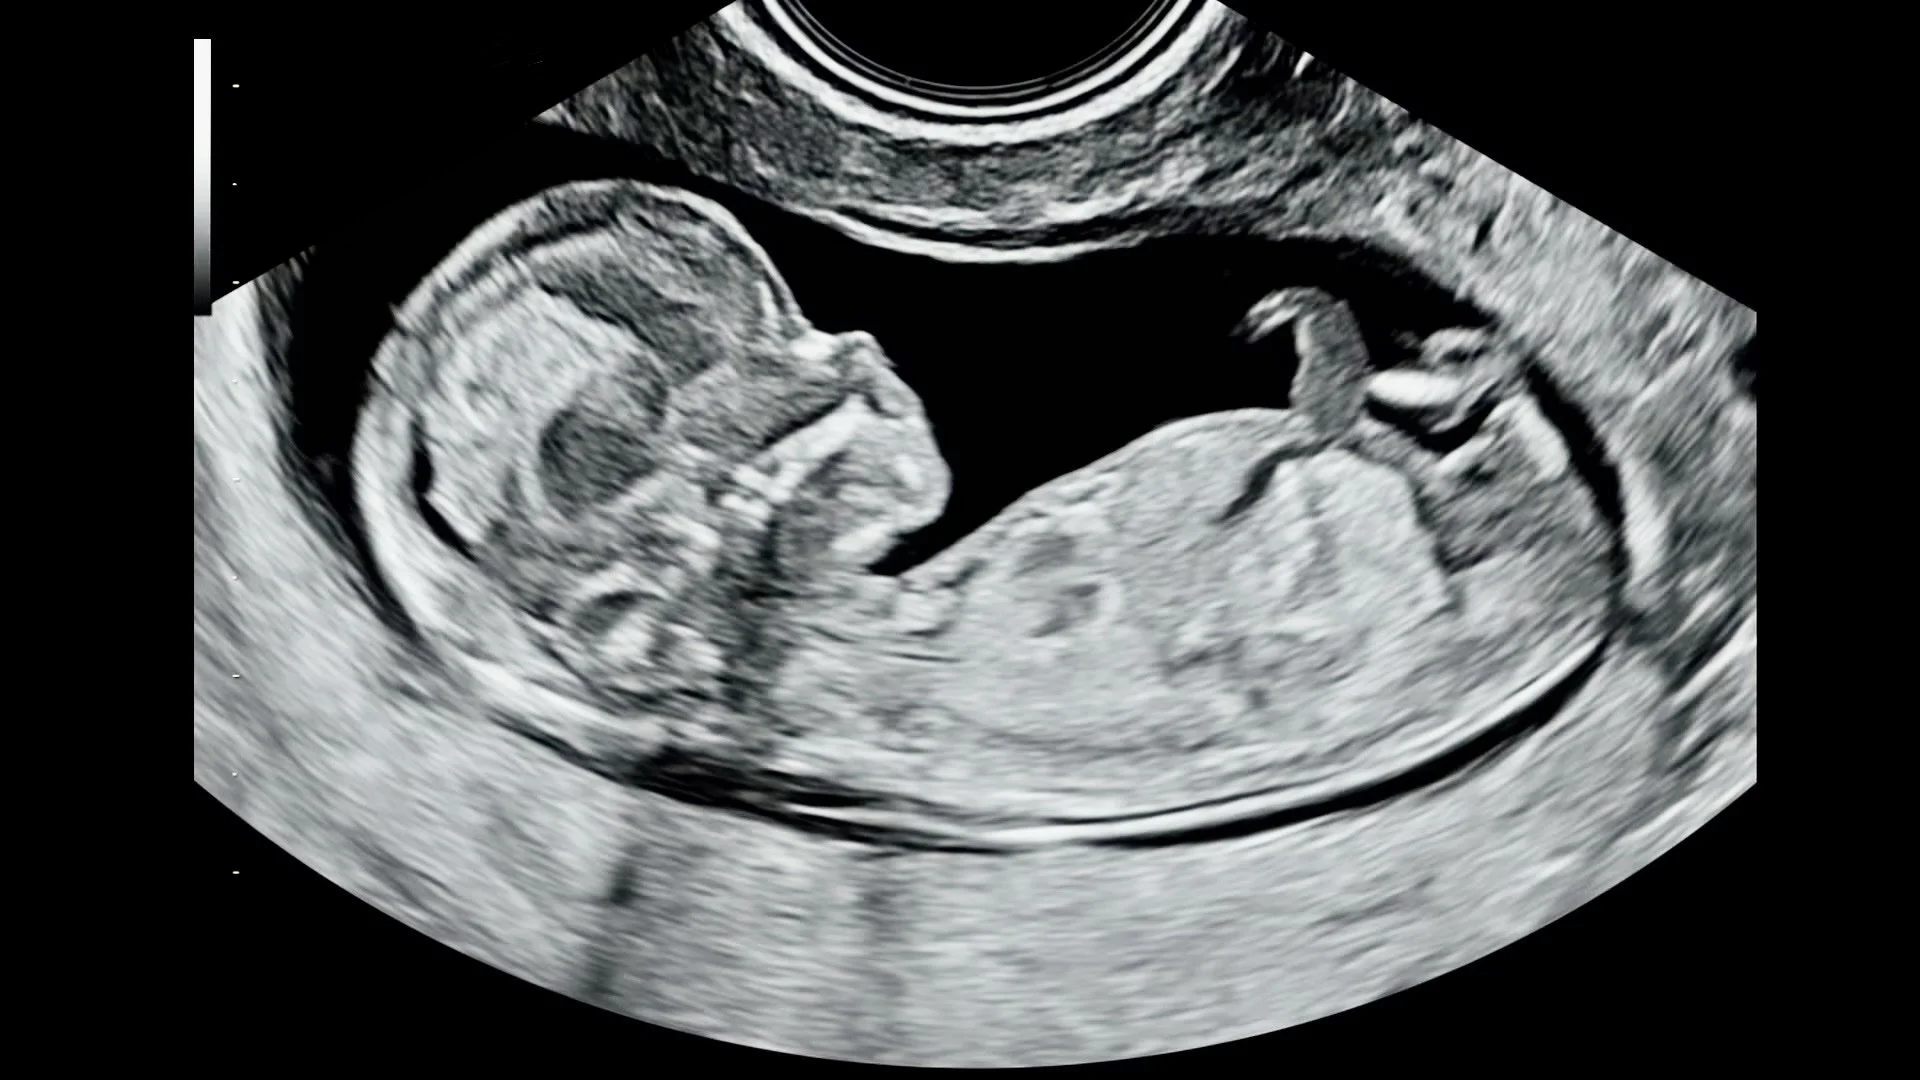

A 2D Pregnancy Ultrasound at Cedar allows you to see your baby’s tiny movements in real time.

Performed by a medical Sonographer using advanced ultrasound technology, our 2D scans are designed for reassurance, bonding, and beautiful keepsakes in a calm, boutique setting.

At Cedar, 2D scans go beyond standard black and white, using enhanced contrast and refined shades for clearer, more detailed images.

• 2D ultrasound is the classic real-time imaging that shows your baby in black-and-white motion. It allows you to watch your baby move, see their profile, limbs, and heartbeat, and experience that first powerful connection.

At Cedar, we elevate traditional 2D imaging with modern technology and expert technique to deliver clearer detail and a more meaningful experience than standard settings.